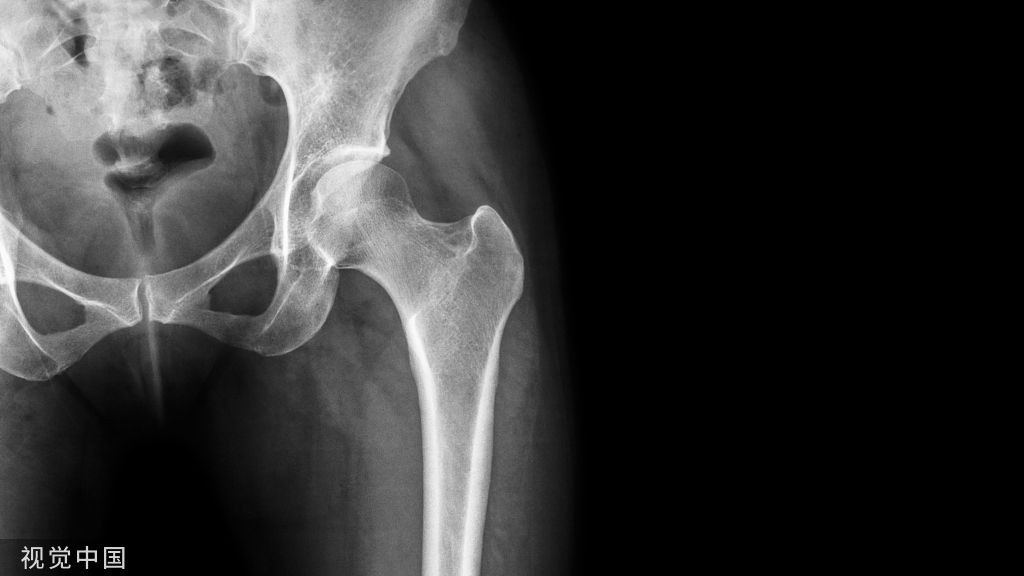

图3 一例92岁股骨粗隆间骨折患者,可见在正位片及侧位片上,骨折均良好显示。